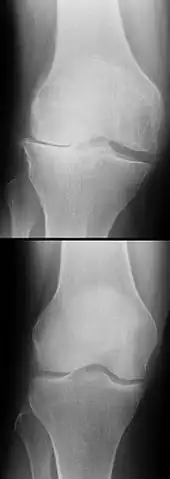

Procédés d'imagerie

Le diagnostic peut être confirmé par imagerie (IRM). Mais il faut noter que l'interprétation de l'IRM seule pour le diagnostic de rupture de LC conduit à 20 % de faux diagnostics. Cela dépend des images de coupe et de la position appropriée du genou pendant l'IRM. Le radiologue doit connaître avec précision les circonstances qui ont conduit à la blessure, et avoir aussi une bonne expérience de l'étude d'une articulation blessée, pour éviter les faux diagnostics. Pour comparer avec l'IRM, le taux d'erreur du test de Lachman, bien plus simple à accomplir, n'est que de 10 %[106],[107],[108],[109]. L'IRM est donc généralement moins sensible et moins spécifique que l'examen clinique par un orthopédiste qualifié[110]. Le résultat de l'IRM n'a que relativement rarement une influence sur la formulation finale du diagnostic[111] et ne devrait pas servir de remplacement pour une anamnèse soigneuse et la palpation[112]. Plusieurs études arrivent à la conclusion que l'IRM n'a de sens que pour des blessures complexes difficiles à expliquer, et là, pour éviter de poser un diagnostic négatif[113],[114],[115].

Les radios n'apportent aucune contribution immédiate au diagnostic de rupture de LC. Les deux LC sont invisibles à la radio, déchirés ou non. La seule utilité de la radio ne peut servir qu'au diagnostic des complications osseuses possibles.